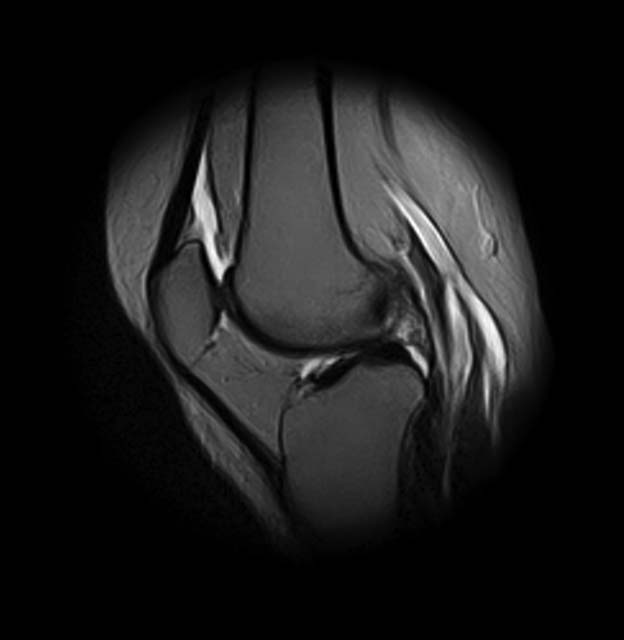

Женщина 45 лет, в течение 5 лет отмечает боли в передне-наружном отделе левого коленного сустава, при повороте туловища и фиксированной стопе, а также при спуске по лестнице боли усиливаются. Клинически - болезненность в проекции переднего рога и тела латерального мениска. Но меня смущает МРТ - нет ли кистозного перерождения и кисты мениска?

добрый день! Не очень понятен принцип, по которому отбирались снимки МРТ. Большинство из них не показательны. Вижу пока только повреждение хряща на феморопателлярной поверхности. Хлтелось бы посмотреть диск целиком

На снимках повреждений наружного мениска не вижу и кисты мениска не вижу. Есть повреждение хряща на передней поверхности внутреннего мыщелка бедра. Вполне может оказаться, что повреждение лоскутное. А какая консервативная терапия проводилась?